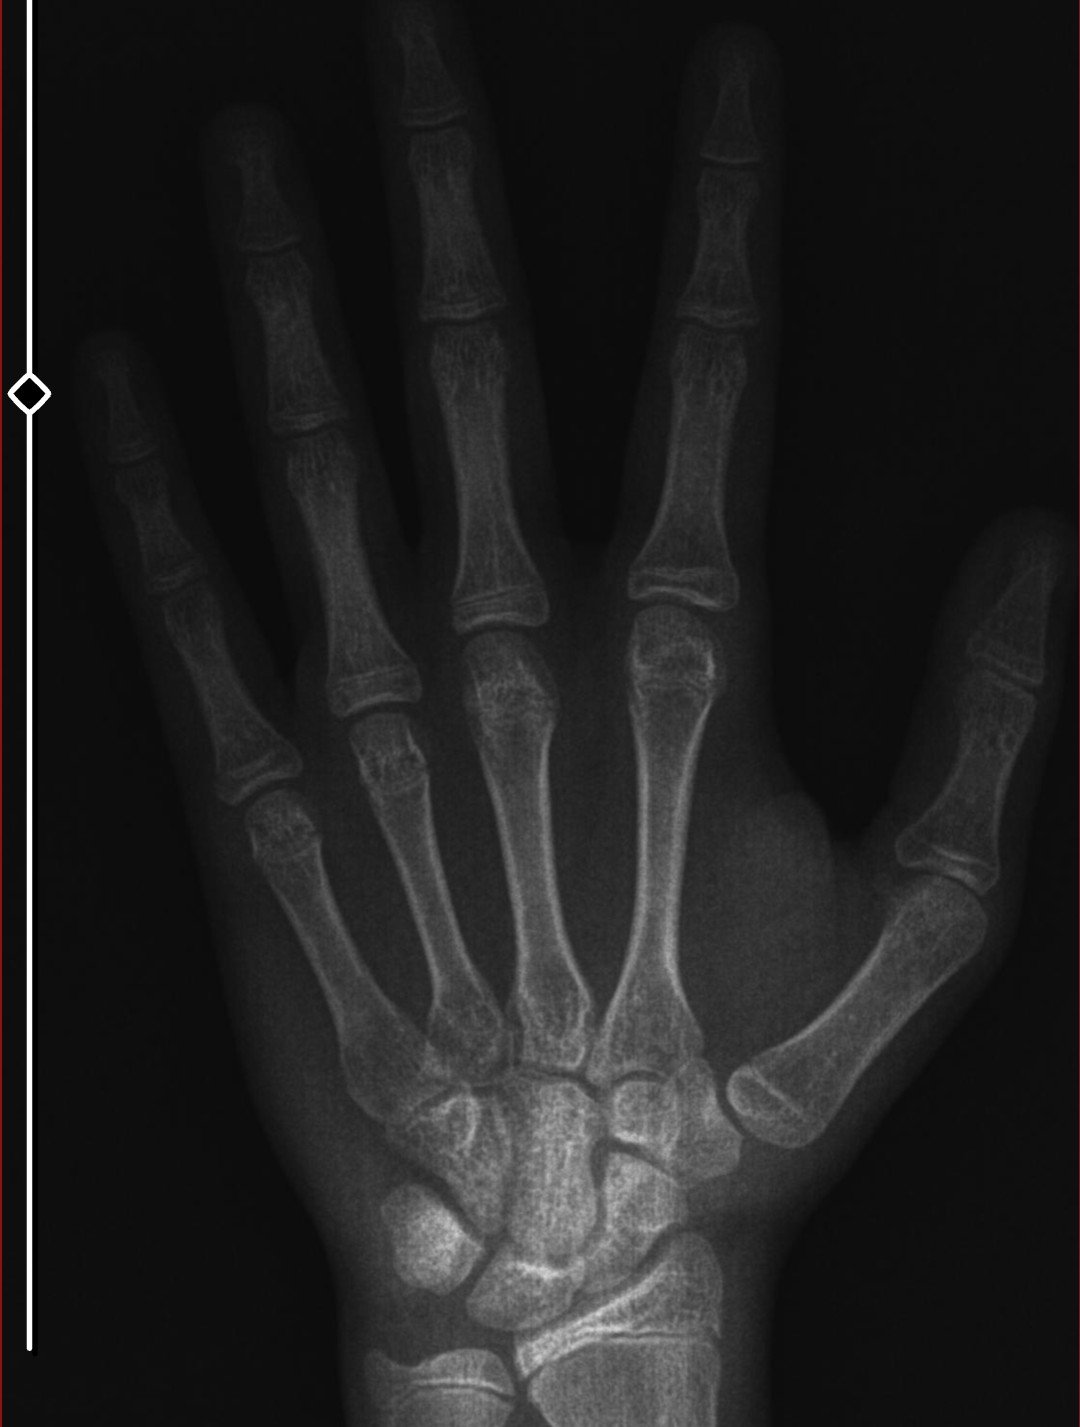

e plaklarım da o kadar açık değil yani 5-6 ay önce aşşadaki gibiydi

röntgen var mı ve ergenliğin ne zaman nasıl başladı (bir referans ver örnegin koltuk altı kili su su yasta cikti diye)

Boyları kesin annemin babamın röntgen yok ergenlikte falan boyu takmiyordum blackpilli falan 16 da koltuk altı kili çıkmaya basladi çok az da sakal çenede o zamanlar boyum 1.75 falandi suan 18 im boyum 1 senedir hiç uzamadi ayakkabı numarası da sabit 1 senedir durdu boy uzaması yani 1.79 da

bi röntgen çektirsene çok garip geldi durumun 16'da koltuk altı ne la ve 17'de uzaman durmuş?

bazılarında kılların zamanlaması çok farklı olabiliyor farkındayım ama yine de fazlasıyla garip

benimde babamın kemik yapısı çok maskülen fakat el genetiğim anneme çekmiş. ellerim seninkiyle aynı, %80 genetik ve 9-10 yaşından sonra parmaklar artık uzamaz yapacağın tek şey kalın ve dolgulu parmaklar/eller için çalışmak. gh ve test arttırmaya bak ellerin ve parmakların kalın, kaslı, damarlı ve çıkıntılı görünecektir uzunluğa fazla takma zaten düzeltemezsin kemik yoğunluğuna odaklan